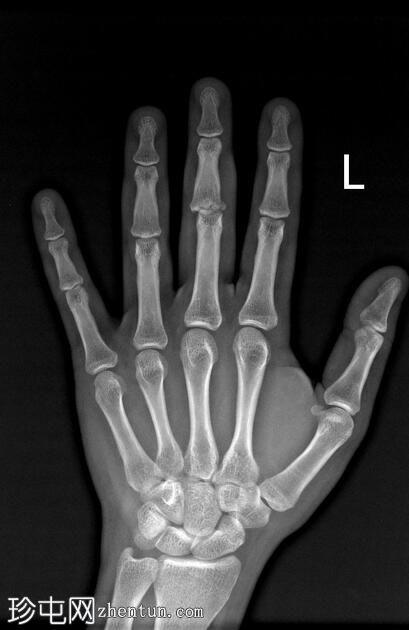

左

手外

伤。

X线片

正位

可见第三指中节指骨基底部轻微移位骨折,延伸至近端指间关节(PIP关节),并伴有软组织肿胀。

第三指中节指骨基底部轻微移位骨折,延伸至近端指间关节(PIP关节)指骨,并伴有软组织肿胀。